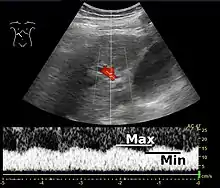

Ultrasound is routinely used in the evaluation of cirrhosis. It may show a small and nodular liver in advanced cirrhosis along with increased echogenicity with irregular appearing areas. Other liver findings suggestive of cirrhosis in imaging are an enlarged caudate lobe, widening of the fissures and enlargement of the spleen. An enlarged spleen, which normally measures less than 11–12 cm in adults, may suggest underlying portal hypertension. Ultrasound may also screen for hepatocellular carcinoma, and portal hypertension, by assessing flow in the hepatic vein. An increased portal vein pulsatility is an indicator of cirrhosis, but may also be caused by an increased right atrial pressure.[47] Portal vein pulsatility can be quantified by pulsatility indices (PI), where an index above a certain cutoff indicates pathology:

| Average-based | (Max – Min) / Average[47] | 0.5[47] |

| Max-relative | (Max – Min) / Max[48] | 0.5[48][49]–0.54[49] |